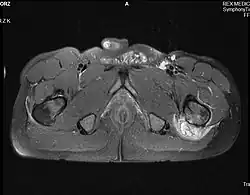

- chrzęstniakomięsak powierzchowny (chondrosarcoma periphericum) – wyrasta z powierzchni kości w obręb otaczających tkanek, najczęściej zajmując kości miednicy i proksymalną część kości udowej; zazwyczaj rośnie powoli

- chrzęstniakomięsak mezenchymalny (chondrosarcoma mesenchymale) – zwykle rozwija się w kościach twarzy i miednicy; przebieg jest niekorzystny

- chrzęstniakomięsak odróżnicowany (chondrosarcoma dedifferentiatum) – z reguły rozwija się w kościach miednicy, kości udowej i ramiennej; przebieg też jest niekorzystny, 90% chorych umiera do 2 lat po zakończeniu leczenia